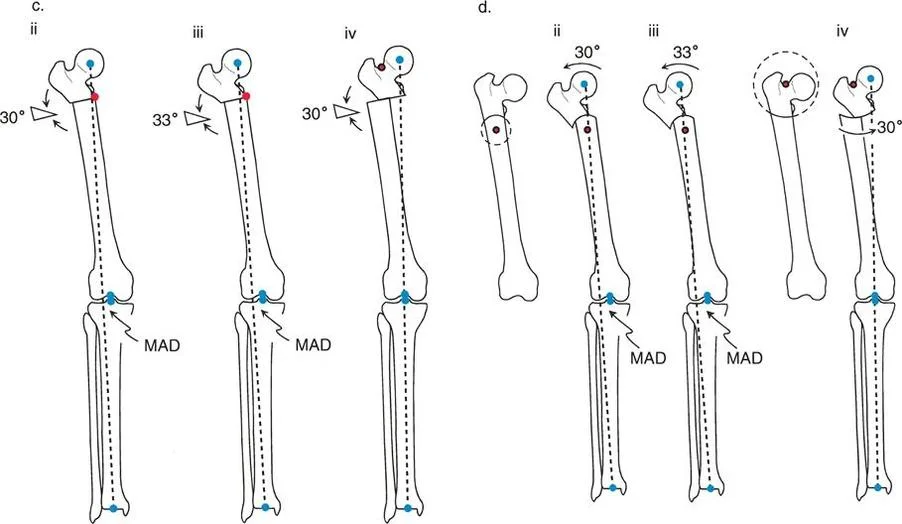

مركز دوران الانحراف (CORA)

يعتبر CORA خاصية أساسية للتشوه في العظم. يُعرّف بأنه نقطة تقاطع خط المحور الميكانيكي (أو التشريحي) القريب وخط المحور الميكانيكي (أو التشريحي) البعيد.

* CORA الحقيقي: هو القمة التشريحية الفعلية للتشوه.

* CORA الحل (Resolution CORA): نقطة نظرية تُستخدم في التشوهات متعددة المستويات حيث تتقاطع المحاور القريبة والبعيدة النهائية، وقد لا تقع هذه النقطة داخل العظم نفسه.

محور تصحيح الزاوية (ACA)

بينما يعتبر CORA حقيقة تشريحية ثابتة، فإن ACA يقع جزئيًا تحت سيطرة الجراح. يمثل ACA النقطة المحورية التي يدور حولها الجزء البعيد من العظم لتحقيق التصحيح.

* الموضع الأمثل: يجب أن يكون ACA موجهًا بشكل عمودي على مستوى التشوه ويمر مباشرة عبر CORA.

مستوى قطع العظم (Osteotomy Level)

مستوى قطع العظم (الشق الجراحي) يقع بالكامل تحت سيطرة الجراح. تحدد العلاقة الهندسية بين مستوى قطع العظم، وACA، وCORA النوع الدقيق للتصحيح الناتج، وتحدد ما إذا كان سيحدث تشوه ثانوي غير مقصود (مثل الانزياح غير المرغوب فيه).

إن فهم العلاقة المكانية بين القطع، والمفصلة، وقمة التشوه هو سر التصحيح الخالي من العيوب. تحدد قواعد بالي لقطع العظم النتائج الميكانيكية لخطتك الجراحية:

القاعدة الذهبية الأولى: القطع والمفصلة عند مركز الانحراف

عندما يمر كل من قطع العظم وACA مباشرة عبر CORA، يتم تصحيح التشوه الزاوي بشكل مثالي. يتم استعادة المحور الميكانيكي، ولا يوجد انحراف في المحور الميكانيكي (MAD)، وتبقى أجزاء العظم القريبة والبعيدة متوازية تمامًا. هذا هو السيناريو المثالي، والذي غالبًا ما يتحقق بقطع عظم وتدي بسيط (فتح أو إغلاق) عند قمة التشوه.

القاعدة الذهبية الثانية: المفصلة عند مركز الانحراف والقطع بمستوى مختلف

في بعض الأحيان، قد يكون قطع العظم مباشرة عند CORA غير ممكن سريريًا بسبب سوء حالة الجلد، أو وجود أدوات جراحية سابقة، أو مشاكل في جودة العظم في منطقة الكردوس/الجذع. إذا بقي ACA عند CORA، ولكن تم إجراء قطع العظم عند مستوى مختلف (أقرب أو أبعد عن CORA)، فسيتم تصحيح التشوه الزاوي بالكامل. ومع ذلك، ستنزاح نهايات العظم عند موقع قطع العظم بالنسبة لبعضها البعض.

* النتيجة السريرية: يؤدي هذا إلى "نتوء" أو تعرج في المحور التشريحي، لكن المحور الميكانيكي العام وتوجيه المفصل يظلان متوائمين تمامًا.